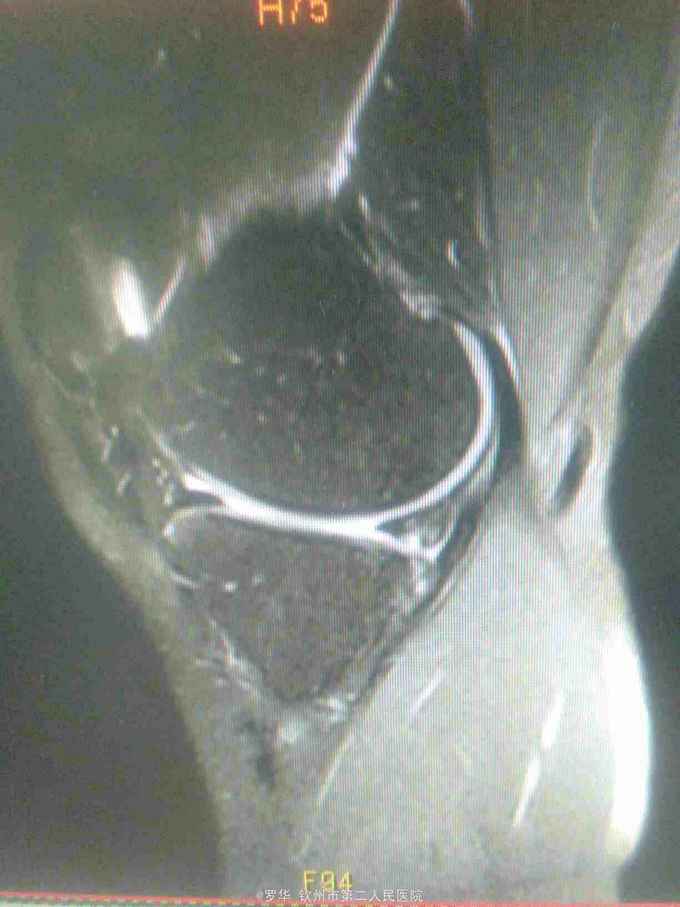

主诉:扭伤致左膝关节活动受限3月余。病史:患者男性,31岁,于入院3月余前扭伤左膝关节,致左膝关节肿痛、活动受限,尚可站立行走,但不能剧烈运动及重体力劳动,曾行磁共振检查提示左膝前交叉韧带损伤,半月板损伤,现为进上一步治疗入院。

查体:左膝关节无明显压痛,前抽屉试验阳性,侧方应力试验、麦氏征、研磨试验均阴性,膝关节屈伸活动可,余查体未见特殊。 辅查:膝关节磁共振提示左前交叉韧带损伤,左膝关节半月板损伤。

诊断:左膝关节前交叉韧带断裂,左膝关节半月板损伤。 治疗:予硬外麻下行左膝关节前交叉韧带重建术。